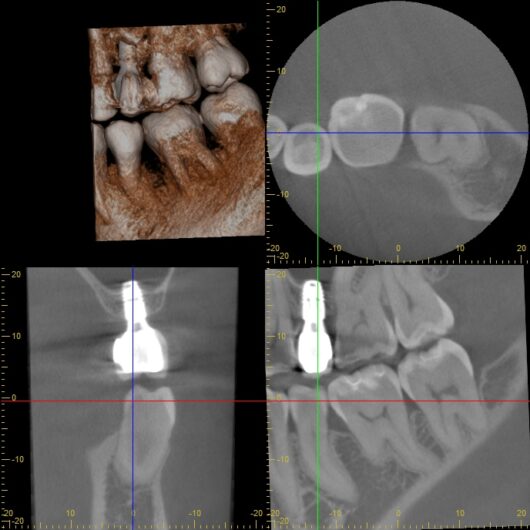

こちらは、インプラント部分をより詳しく見ることができるCT画像です。

短いながらも、インプラントが周りの骨としっかりと結合し、安定した土台となっている様子が確認できます。これにより、Aさんは左右の奥歯で均等に、力強く噛むことができるようになりました。